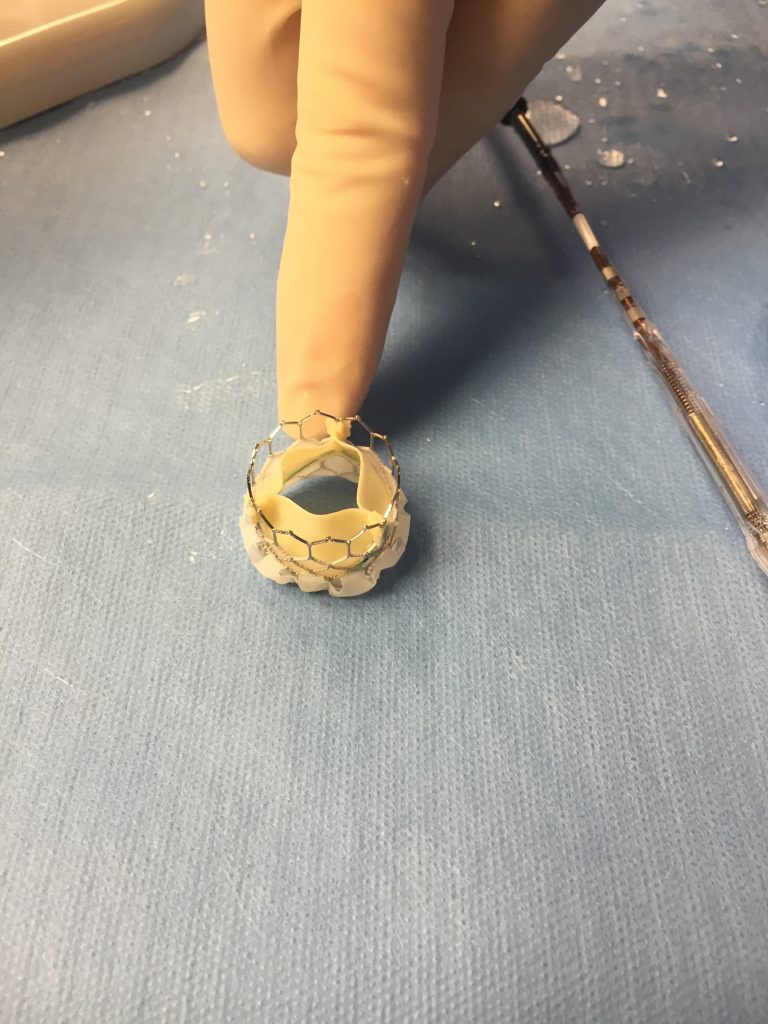

Tavr Faq S Answered By A Cardiologist Myheart Net

Http Pdf Posterng Netkey At Download Index Php Module Get Pdf By Id Poster Id 115936